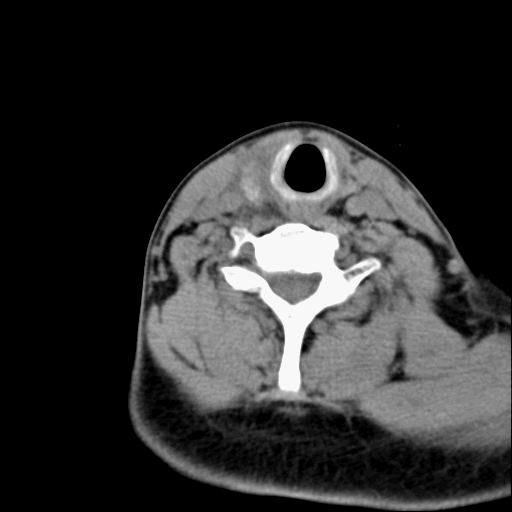

标题: CT23947 右颈部触及00.5x1.5cm质硬长形肿块,疼痛 [打印本页]

标题: CT23947 右颈部触及00.5x1.5cm质硬长形肿块,疼痛

右侧甲状腺腺瘤考虑

甲状腺癌可疑

右侧甲状腺病灶,建议增强或结合b超检查。

右甲状腺占位,建议增强。

甲状腺腺瘤或癌

甲状腺占位  定性有时很难 但无论癌还是腺瘤 还是手术比较好!以下是甲状腺占位的ct鉴别诊断

ct表现:形态不规则的软组织密度肿块,可累及部分或大部分甲状腺组织,密度不均,可坏死、囊变、钙化,增强病灶呈不均匀强化,有局部侵犯或转移时可有颈部淋巴结肿大。

ct表现肿瘤呈稍低密度结节状肿块,边缘光整、锐利病灶均匀强化,少数腺瘤可有钙化。